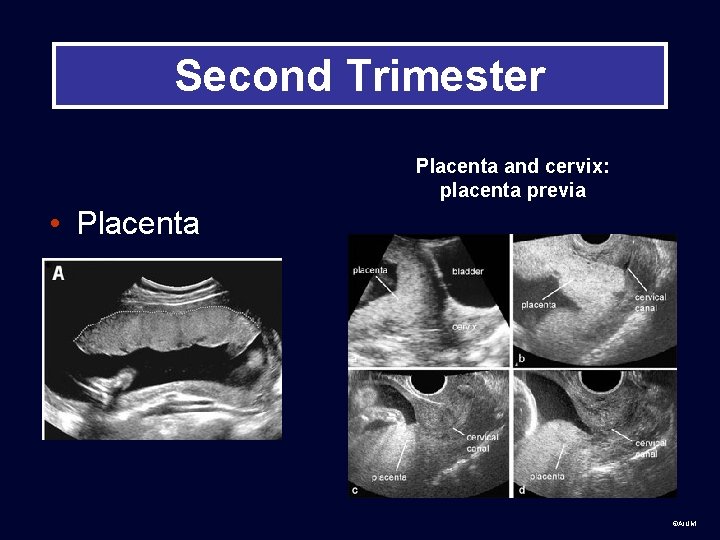

Second Trimester Placenta and cervix: placenta previa • Placenta ©AIUM